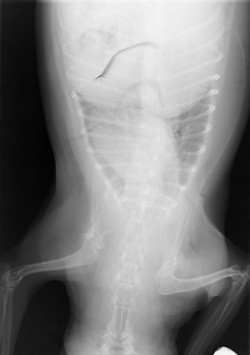

Underexposure, Rough Film Handling

Folding of film results in crescent-shaped artifacts which may be white or black, depending on how roughly the film is mishandled. White marks are pre-exposure, and black marks are post-exposure.